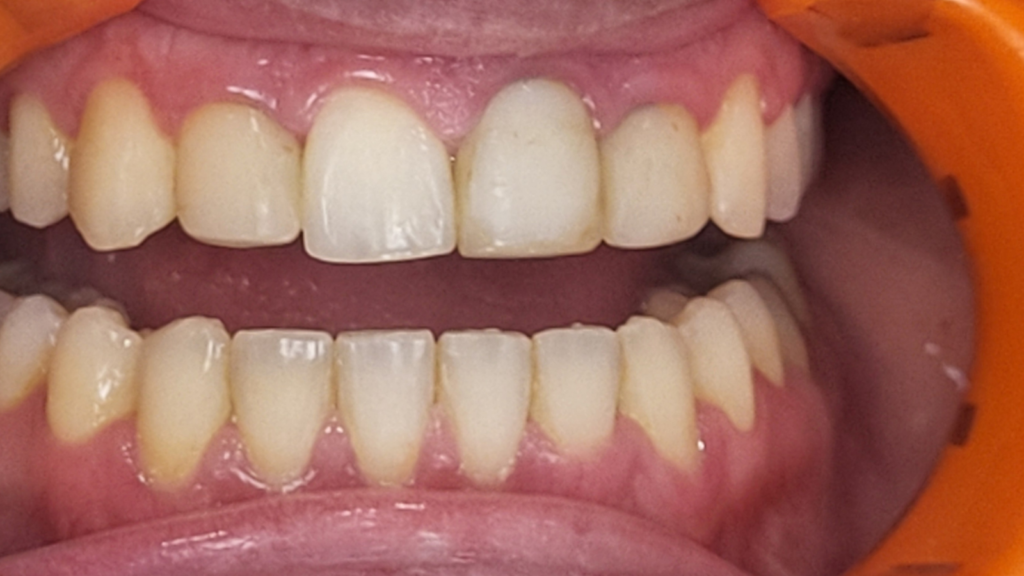

Réhabilitation esthétique après orthodontie : full-zircone & disilicate de lithium

Une jeune patiente arrive en fin de traitement orthodontique pour un déficit esthétique.

La difficulté réside dans la réalisation de prothèses différentes dans le même secteur : jongler avec la full-zircone et le disilicate de lithium.

Ce challenge fut le sujet de mon mémoire du DU d’esthétique de Strasbourg en 2008.

L’expérience et l’investissement dans le digital depuis 2017 rendent le résultat plus prévisible.

Images :